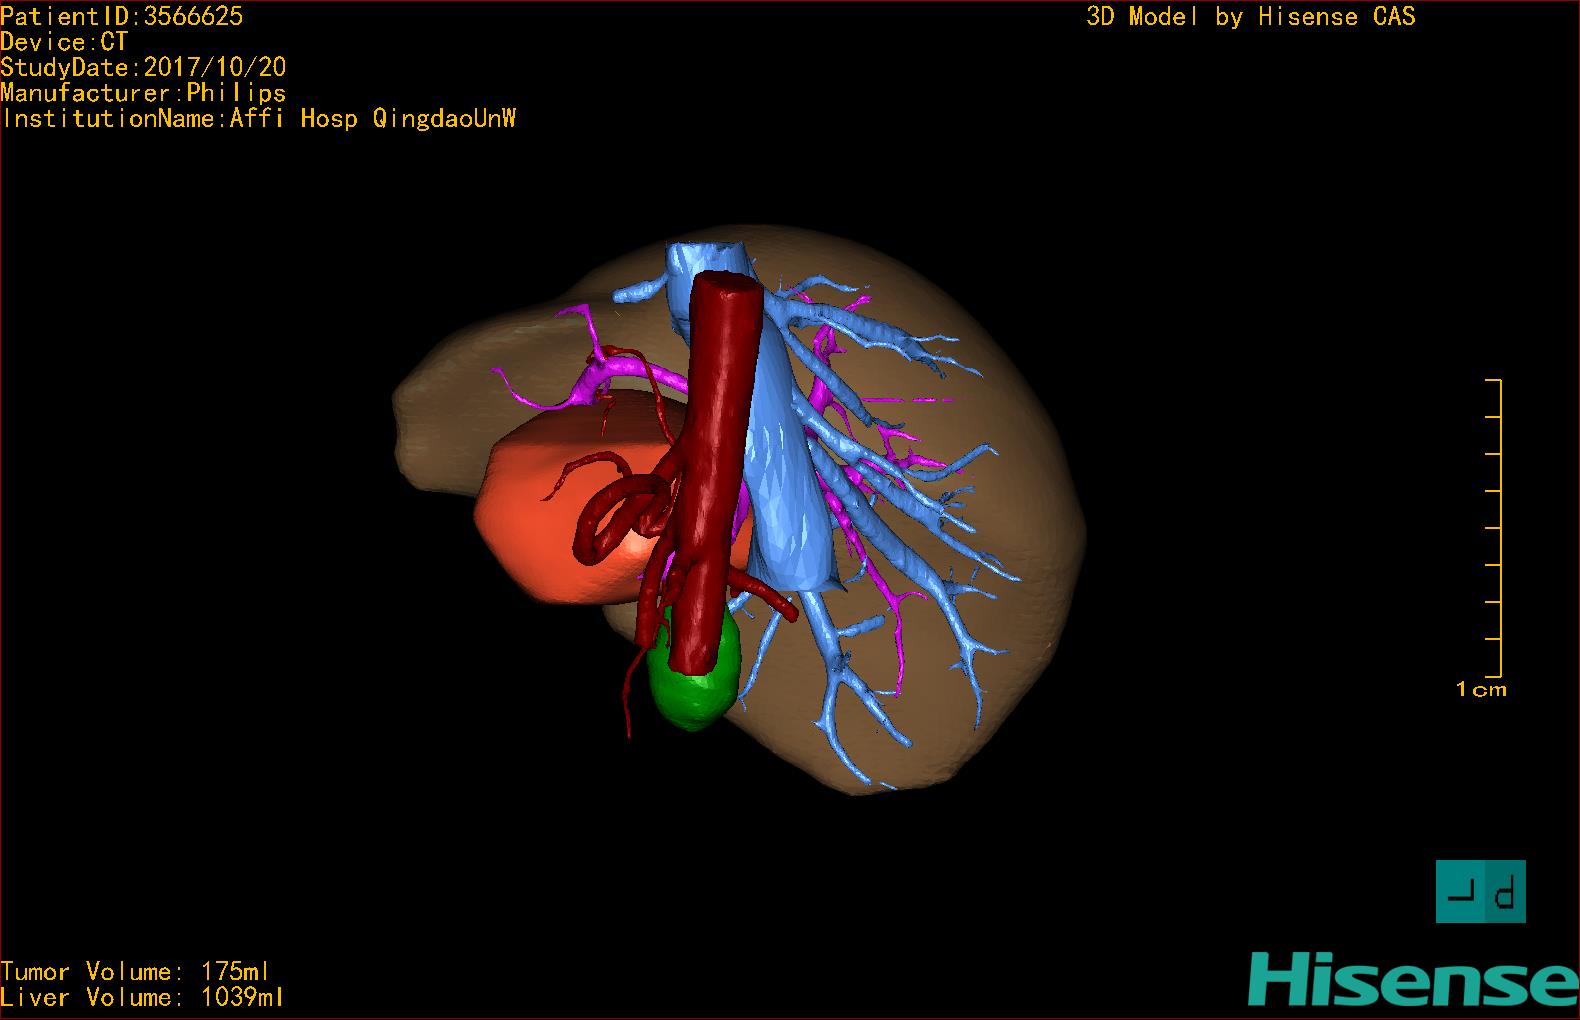

通过调节窗宽窗位调整CT序号,对肿瘤,肝实质,胆囊,下腔静脉,肿瘤,肝动脉、门静脉及肝静脉等进行三维重建;系统自动计算肿瘤体积和肝脏体积。模拟手术操作,自动计算切除肿瘤体积。肝脏体积为1039ml,肿瘤体积为175ml,通过比对40-50岁正常肝脏体积为1423.76±216.93ml,通过术前模拟手术,精准判断切除后剩余肝脏体积能耐受,避免肝衰竭发生。

术前三维重建:

重建图片